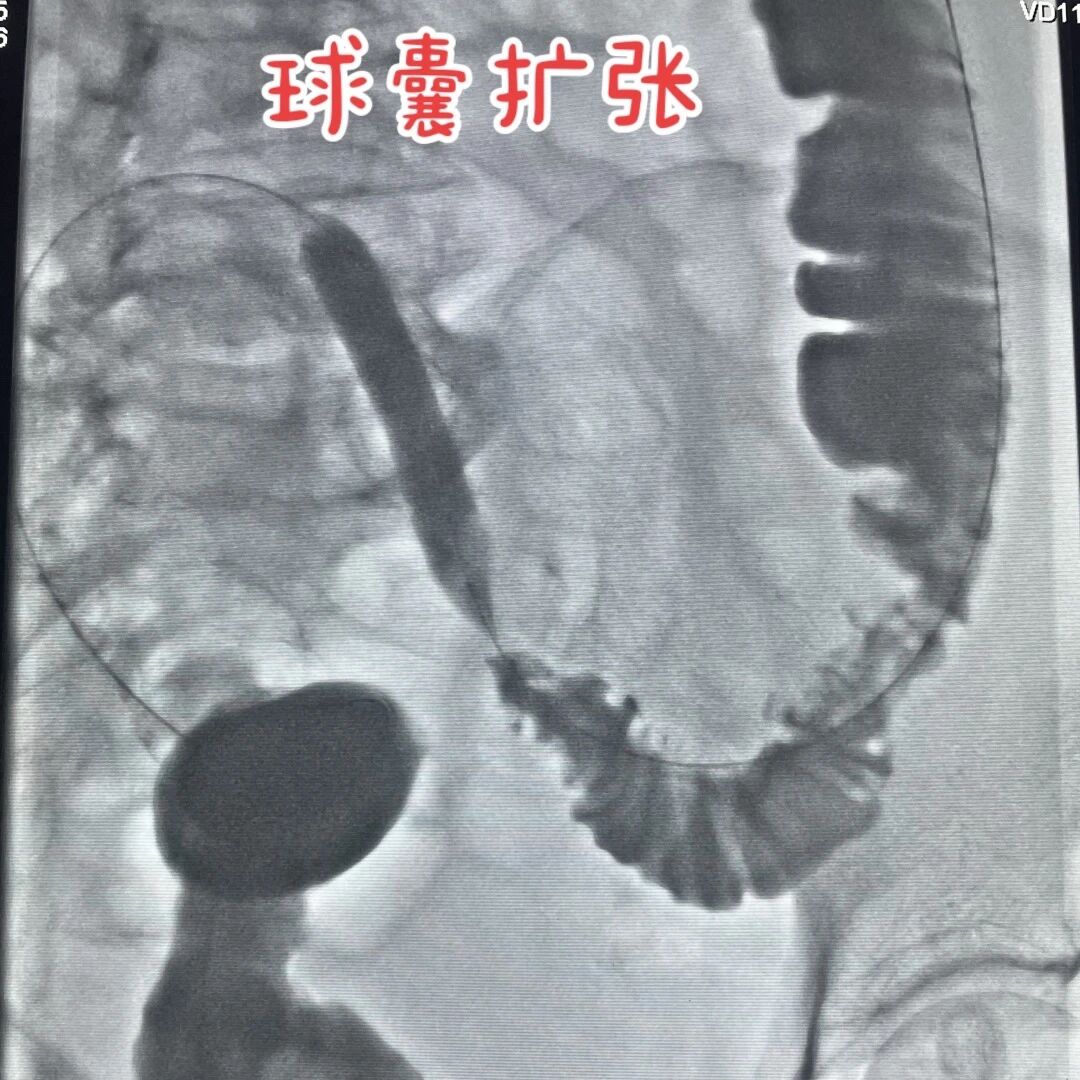

血3.jpg

完善術前準備后,徐燕能博士小心翼翼地從肛門把腸道支架送到梗阻點,慢慢撐開來,把堵塞腸道通道重新打開,讓那些被堵住的食物殘渣和氣體能夠順利通過。整個過程約60分鐘,全程全麻,潘婆婆睡了一覺就結束了,一點沒覺得疼。